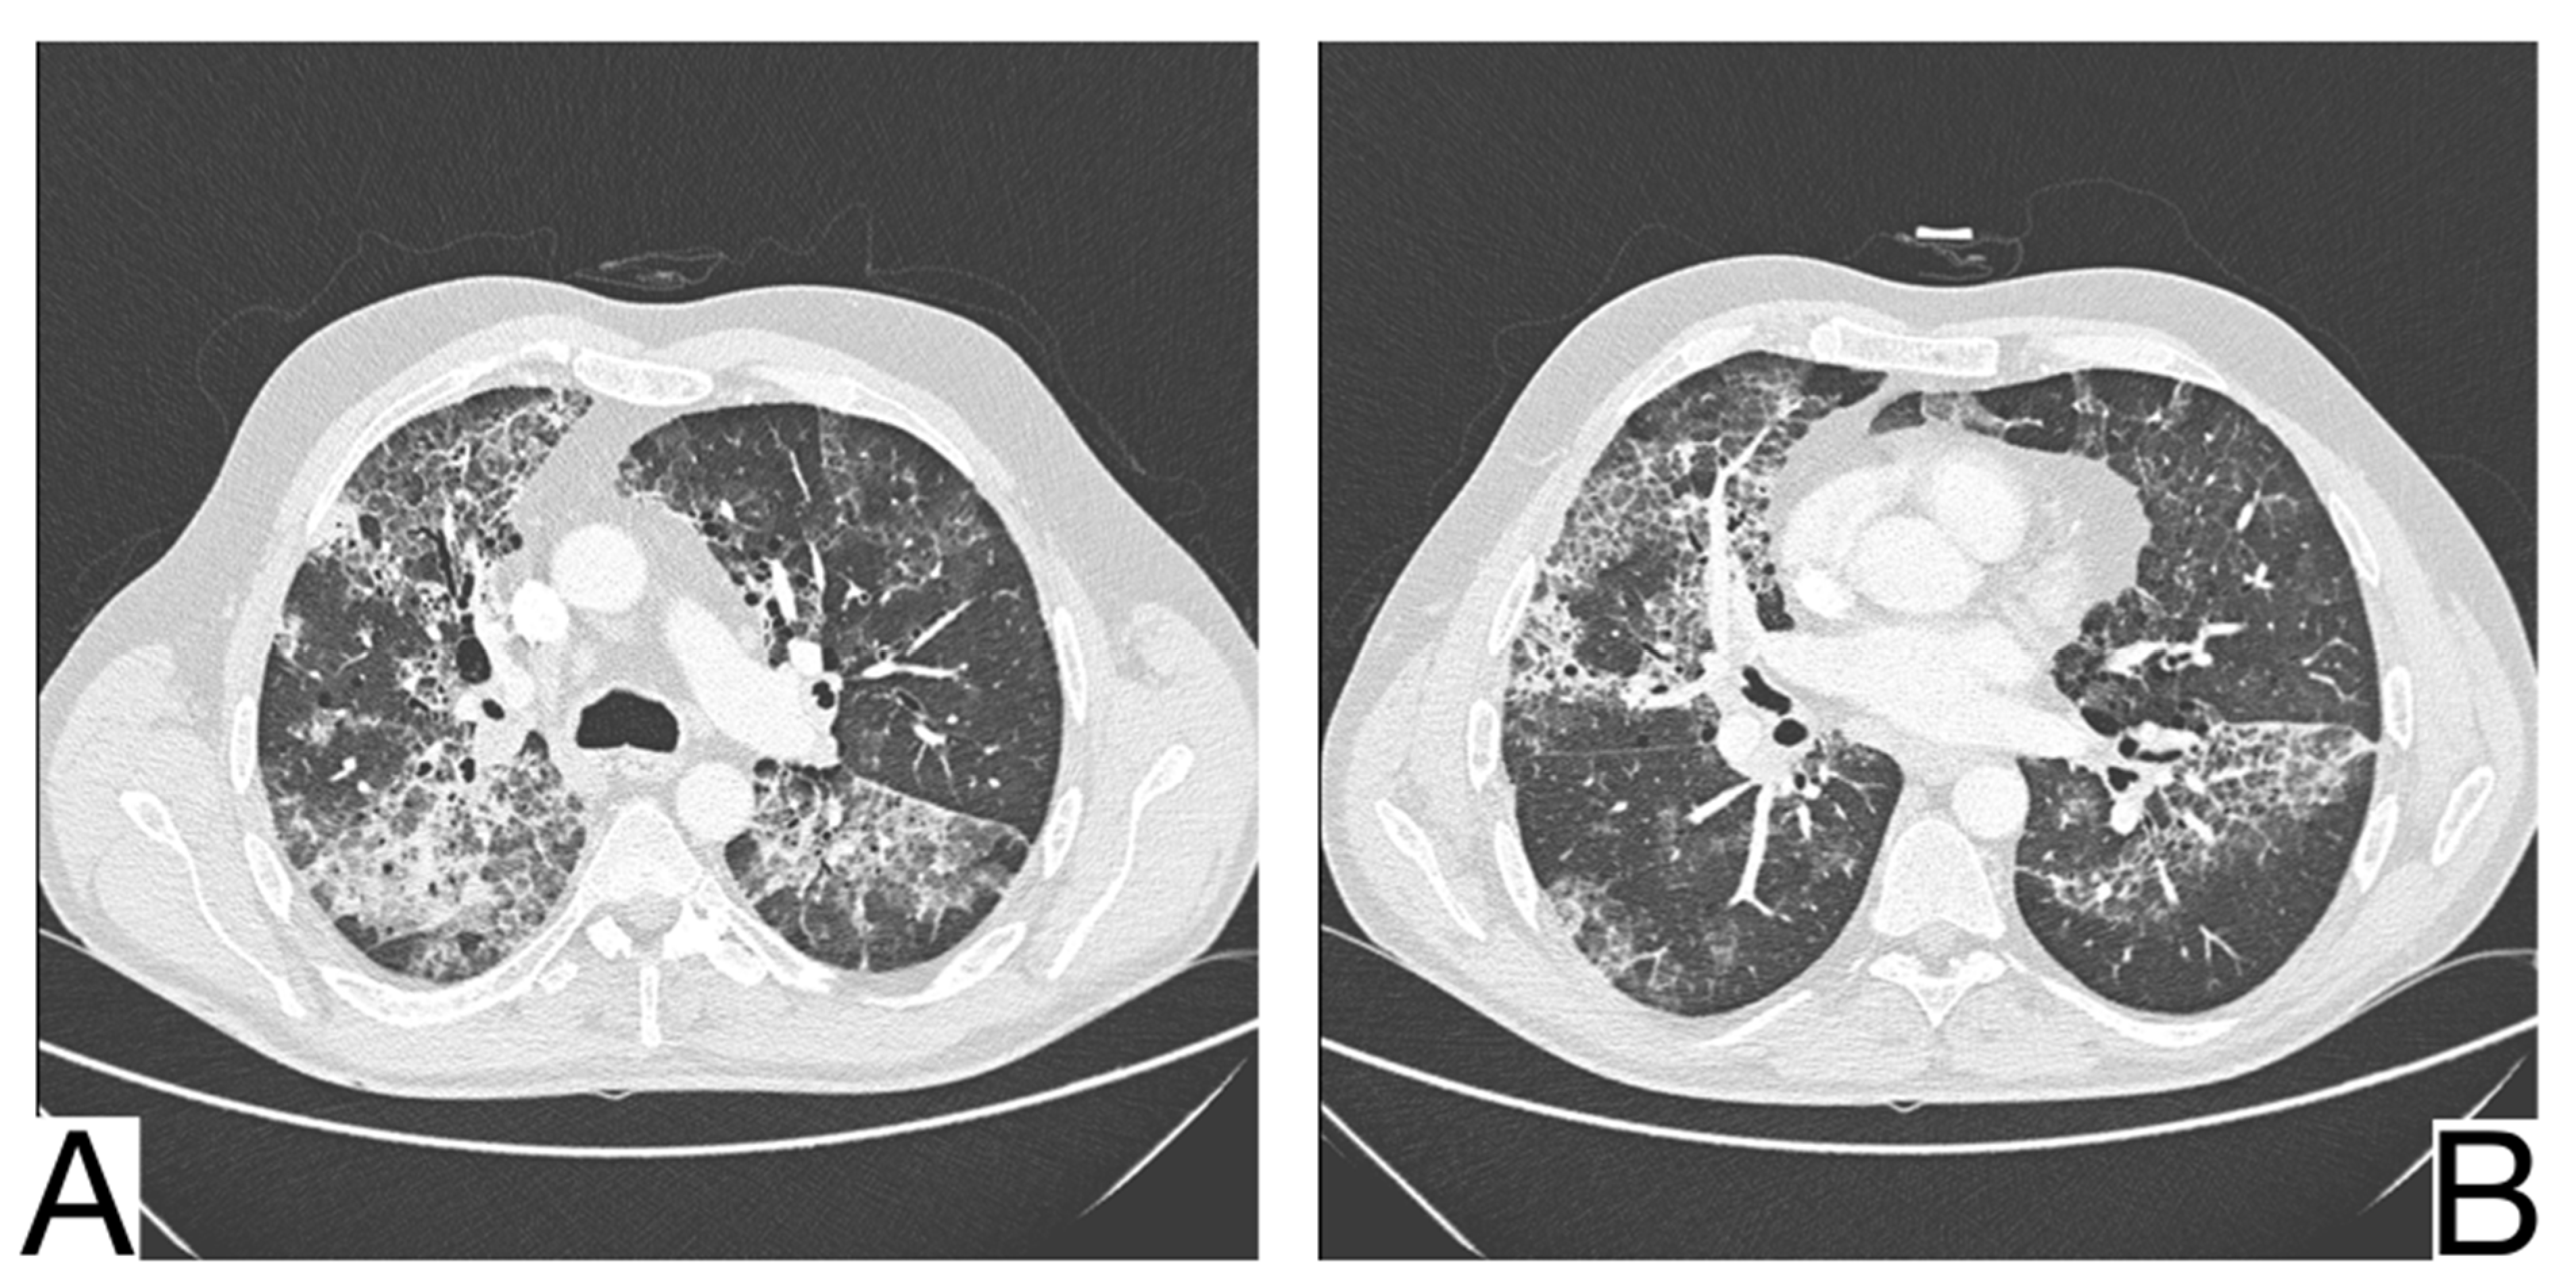

10.10. Pulmonary Alveolar Proteinosis

10.11. Drug-Induced Pulmonary Pathology

10.12. Differential Diagnosis between COVID-19 Pneumonia and Idiopathic Interstitial Pneumonia (IIP)